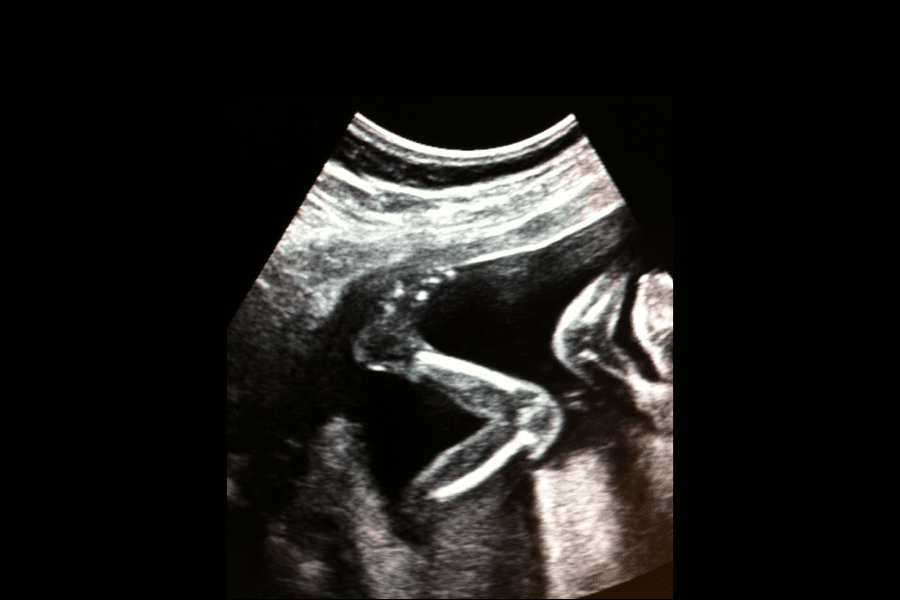

I tidig graviditet rör sig barnet utan att du känner av det, men det är ändå full aktivitet i din livmoder. Med hjälp av ultraljud kan man så tidigt som vecka 7-8 se små rörelser, som att barnet vrider på sitt huvud. Med ultraljud går det också att urskilja andningsrörelser och hur barnet tränar sina lungor redan i graviditetsvecka 11.